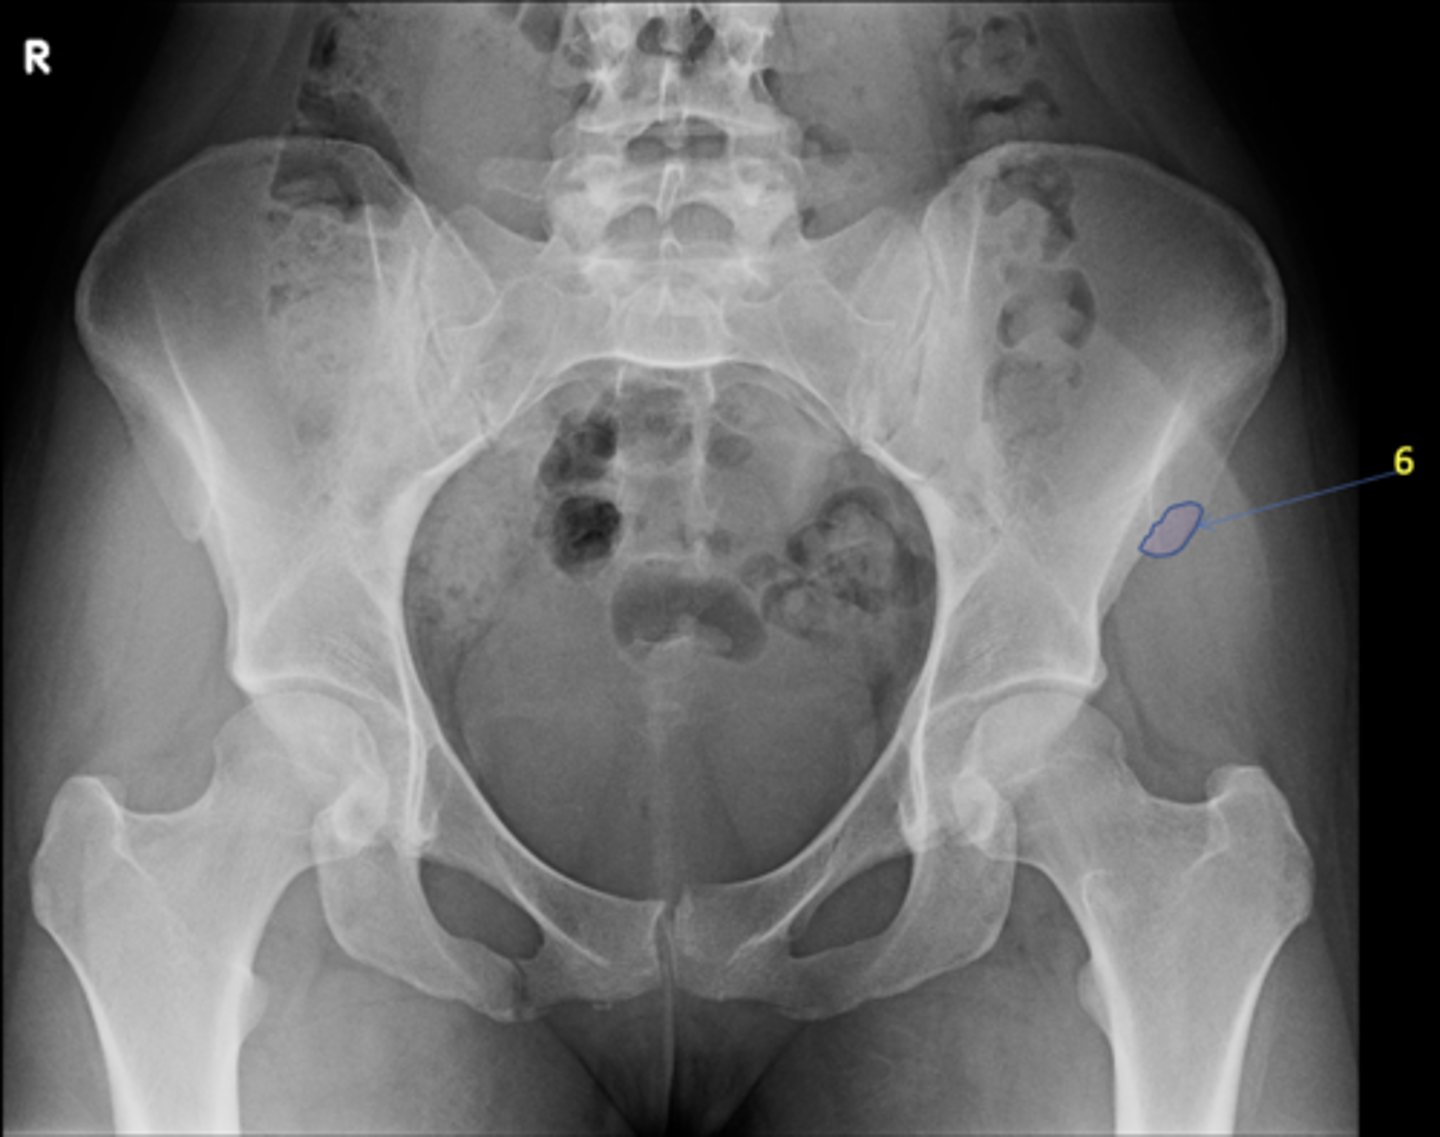

1

New cards

AP pelvis

View?

2

Right lesser trochanter

ID 2

3

Left greater trochanter

ID 3

4

Right iliac crest

ID 4

5

Right iliac fossa

ID 5

6

Left anterior superior iliac spine

ID 6

7

Right ischium

ID 7

8

Left ischial spine

ID 8

9

Right fovea capitis

ID 9

10

Left obturator foramen

ID 10

11

Right posterior superior iliac spine

ID 11

12

Left femoral neck

ID 12

13

Left anterior inferior iliac spine

ID 13

14

Left inferior pubic ramus

ID 15

15

S1 tubercle

ID 16

16

Left sacral ala

ID 17

17

Right femoral head

ID 19

18

Kohler's teardrop

ID 20

19

Right pubis

ID 21

20

Right anterior sacroiliac joint

ID 22 (joint)

21

Left superior pubic ramus

ID 24

22

Right acetabulum

ID 25

23

Right intertrochanteric crest

ID 26

24

Left ilium

ID 27

25

Right ischial tuberosity

ID 28

26

Bladder

ID 29

27

Ascending colon

ID 30